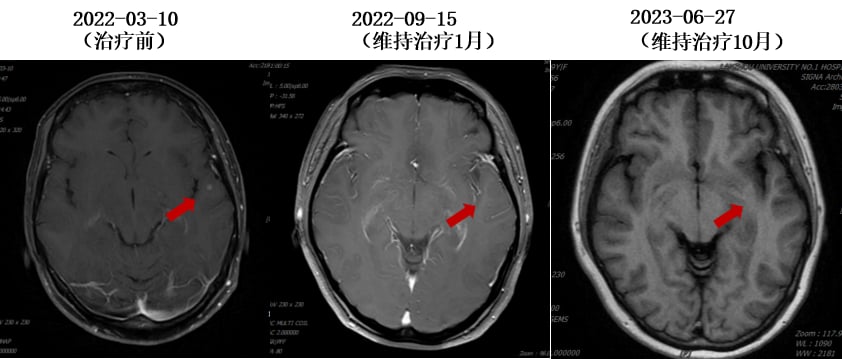

- 骨转移治疗:定期静脉注射唑来膦酸,并口服碳酸钙D3片和骨化三醇进行补钙。

令人惊喜的是,治疗后患者疗效评价为部分缓解(PR),特别是颅内病灶达到了完全缓解(CR),且长期无症状。这充分证明了HER2靶向治疗的强大效果,即使是脑转移这种棘手的情况,全身治疗也能取得显著成效。随后,患者进入维持治疗阶段,使用氟维司群+曲妥珠单抗+戈舍瑞林,病情持续稳定。

3. 脑转移的治疗策略:全身治疗优先

对于脑转移这一棘手问题,专家们一致认为,在全身系统治疗有效控制病灶的情况下,可暂缓局部放疗以避免神经毒性。本案例中,患者通过曲妥珠单抗和德曲妥珠单抗等药物,成功控制了脑转移,甚至实现了颅内病灶的完全缓解。这有力地证实了“全身治疗优先”策略的可行性。建议仅在后续全身治疗失败或出现局部进展时,才考虑放疗干预。